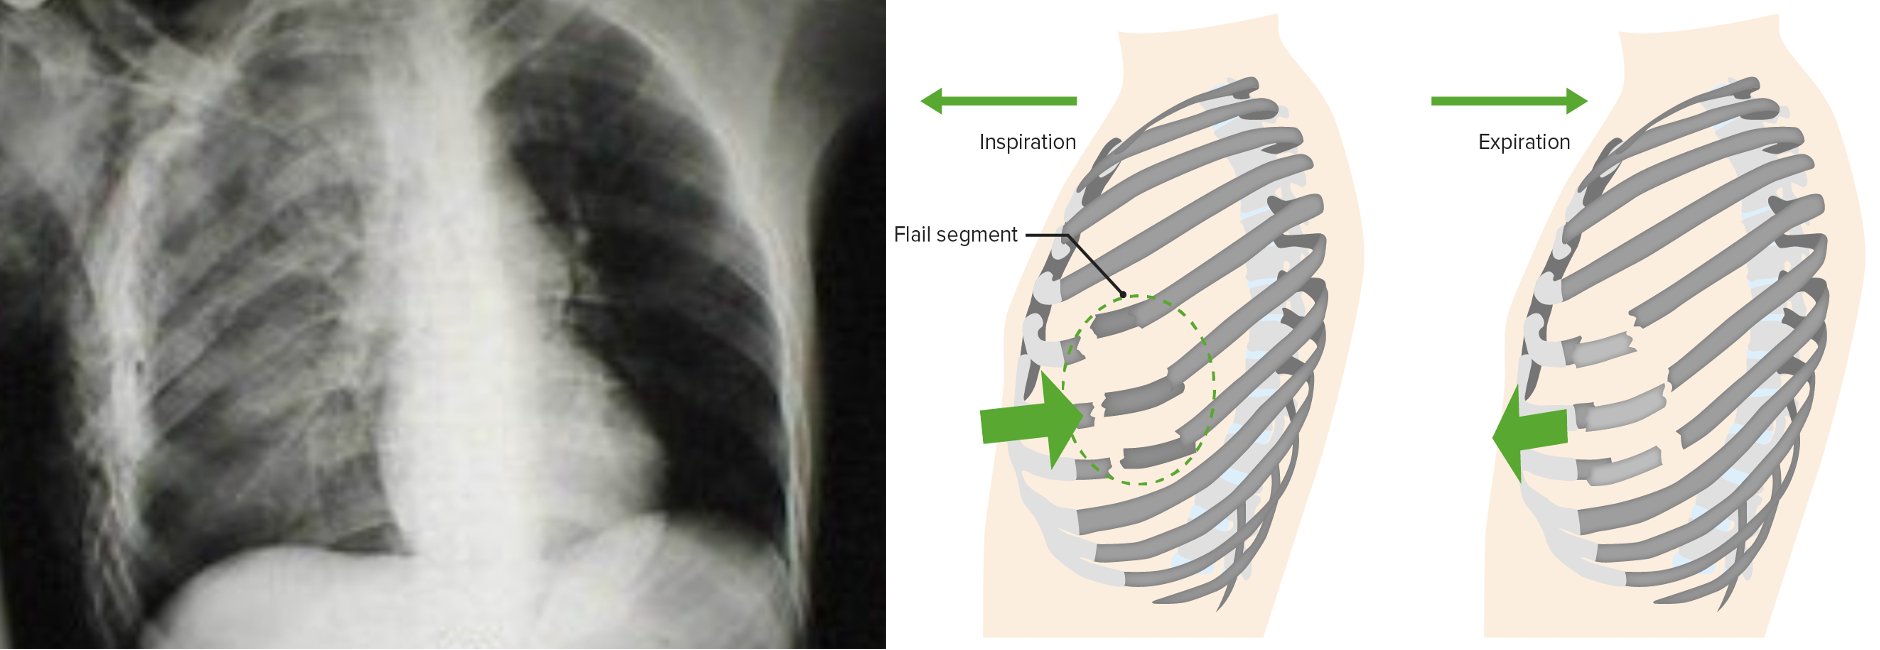

Flail chest with pulmonary contusion

- Three or more ribs fractured in at least two locations

- Paradoxical movement of “free-floating segment” may occasionally compromise ventilation.

- More importantly, an underlying pulmonary contusion may compromise oxygenation or ventilation

- Initial chest x-ray underestimates the degree of contusion

- The lesion evolve with time and fluid resuscitation